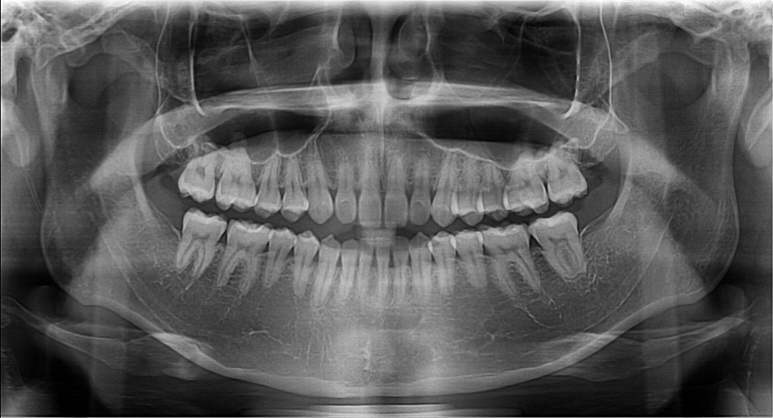

말씀하신 돌출입인지 아닌지는 연조직 사진 등도 모두 필요합니다. 지금은 골격적인 자료들만 있기 때문에 상악이나 하악의 발달 정도가 정상 범위에서 벗어나더라도 밖으로 보이는 연조직에서 차이가 있다면 돌출입이 될 수도 있고 안될 수도 있습니다. 따라서 지금의 자료로는 정확한 판단이 어렵습니다.

지금 자료로 보았을 때 심미적으로 비발치나 발치 교정을 하더라도 큰 변화는 기대하기 힘들 것으로 보입니다.

아래 위 치아의 간격이 2mm 를 이상적인 거리로 봅니다.

많이 부정교합이 심한 편은 아니지만 환자가 볼때 입술이 튀어 나온 것 같아 신경이 쓰인다면 교정으로도 어느정도는 조절이 가능합니다.

발치/비발치 여부는 둘다 가능하니 교정하실 치과에 가셔서 상담 받아보시길 바랍니다. 감사합니다.